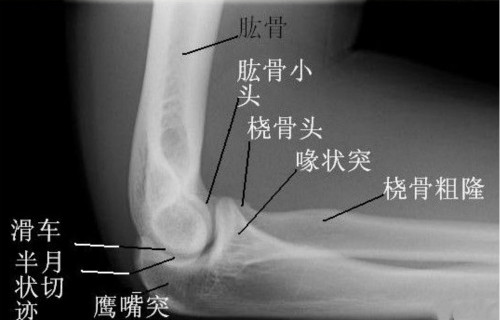

肘关节歌诀

肘关节很特殊,一个囊内包三组;

肱桡肱尺桡尺近,桡环韧带尺桡付;

屈肘三角伸直线,脱位改变能查出。